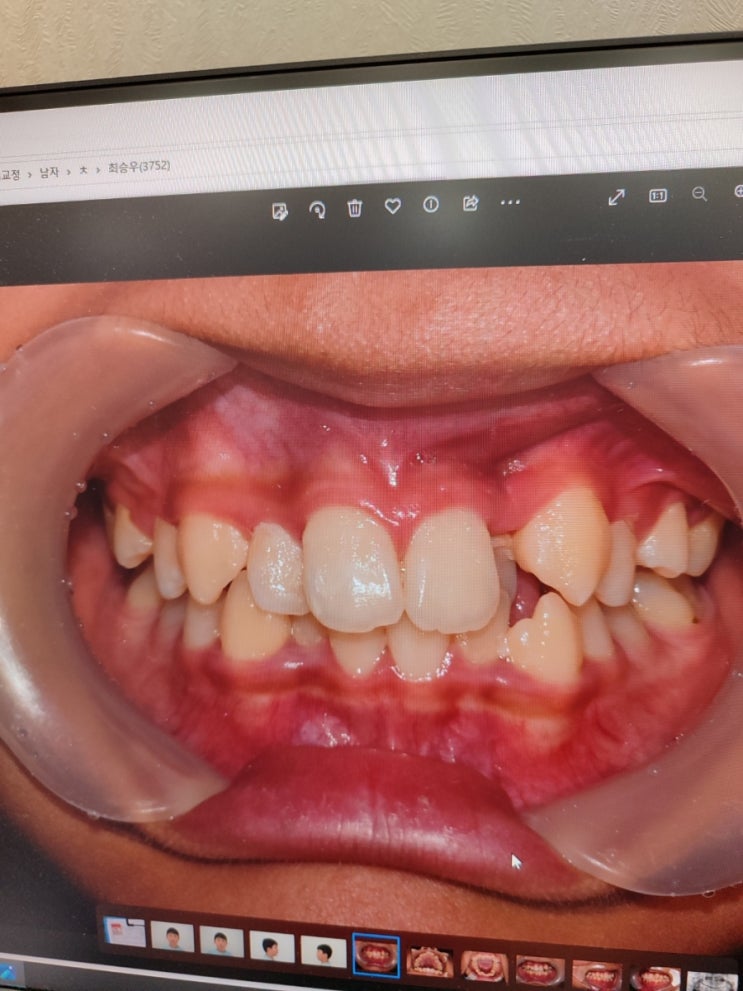

막내 치아교정 3년간의 긴 시간의 끝

교정기간: 11살에 시작 3년 6개월 교정비용: 500만원 (카드,현금동일) 교정병원: 인천 논현동 고운이치과교...